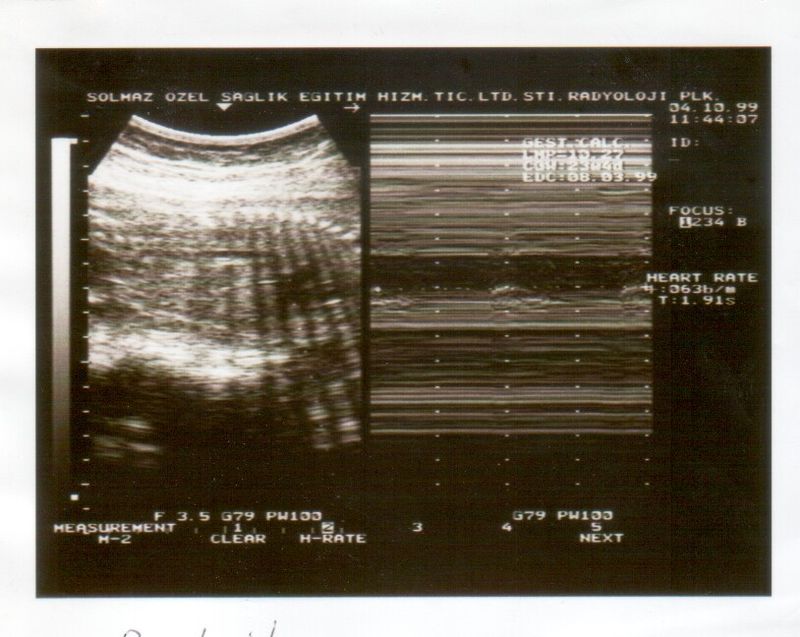

Biophysical Profile Scoring offers a comprehensive assessment of fetal health, combining ultrasound evaluations with a non-stress test. This method checks crucial parameters such as fetal heart rate, movement, breathing, muscle tone, and amniotic fluid volume. The detailed insights provided by BPS help in identifying potential issues early, allowing for timely interventions if necessary.